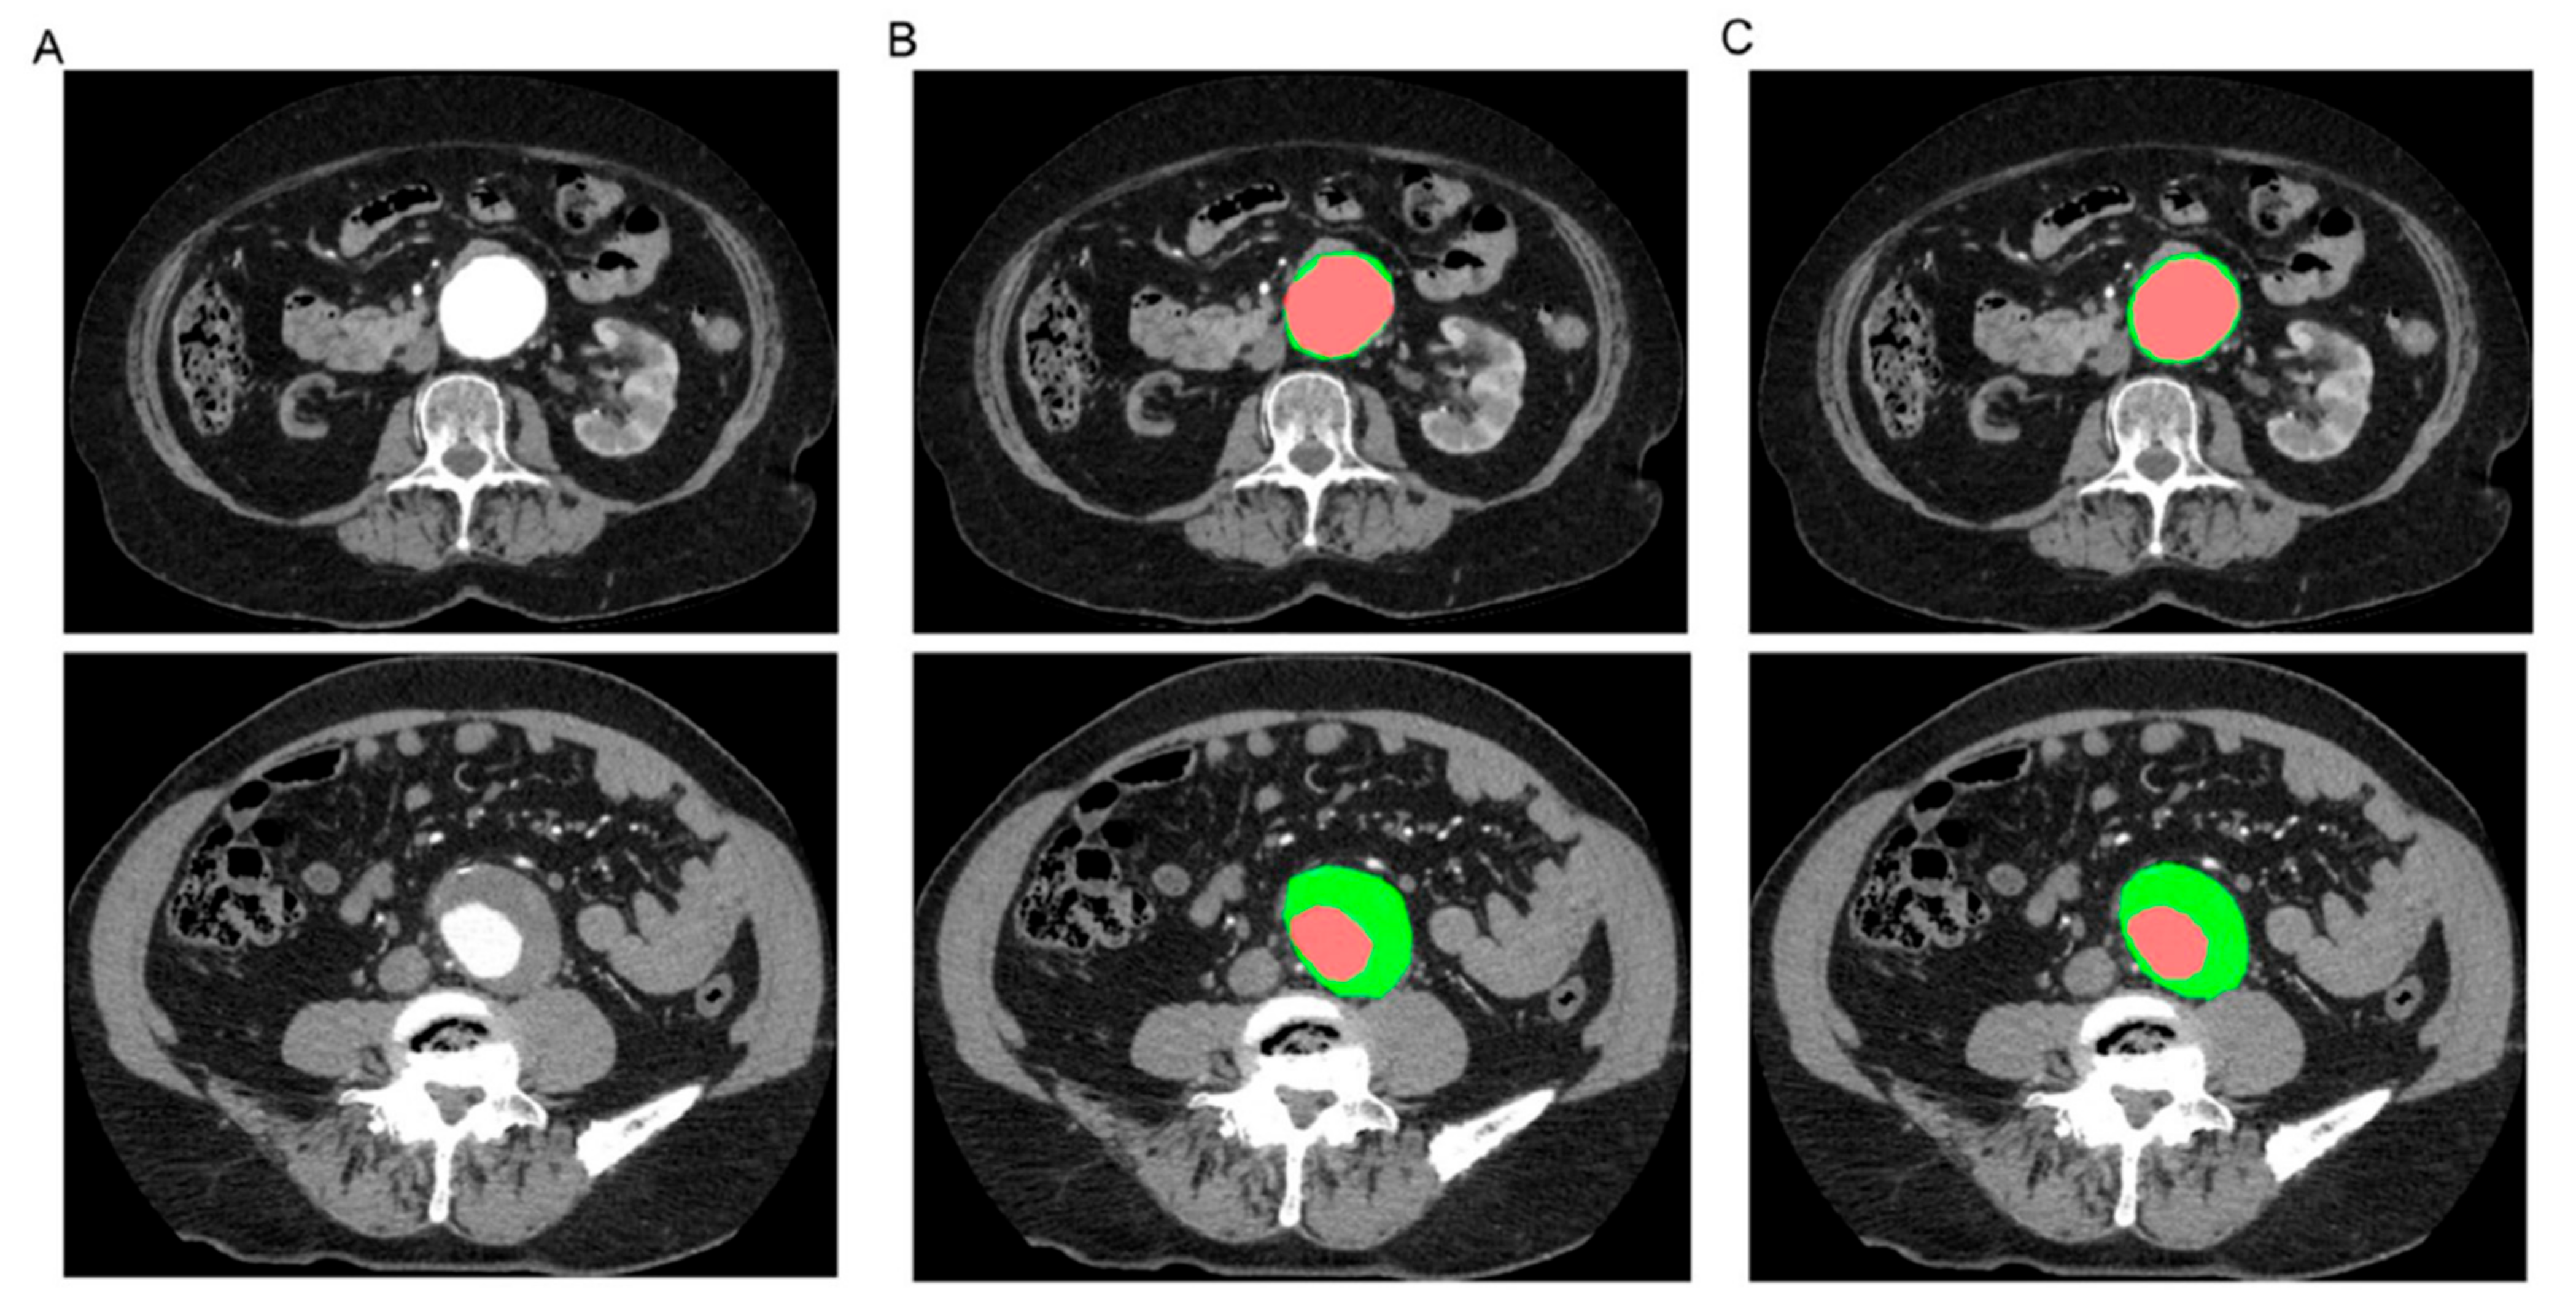

- Lareyre, F.; Adam, C.; Carrier, M.; Dommerc, C.; Mialhe, C.; Raffort, J. A fully automated pipeline for mining abdominal aortic aneurysm using image segmentation. Sci. Rep. 2019, 9, 13750. [Google Scholar] [CrossRef] [PubMed]

- Spinella, G.; Fantazzini, A.; Finotello, A.; Vincenzi, E.; Boschetti, G.A.; Brutti, F.; Magliocco, M.; Pane, B.; Basso, C.; Conti, M. Artificial Intelligence Application to Screen Abdominal Aortic Aneurysm Using Computed tomography Angiography. J. Digit. Imaging 2023, 36, 2125–2137. [Google Scholar] [CrossRef] [PubMed]